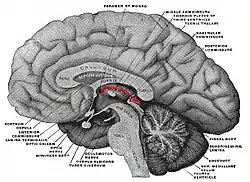

Stria medullaris highlighted in red over the thalamus. Posterior to the thalamus, the highlighted portion is the pineal gland | |